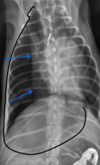

3

Q

what kind of pattern

A

unstructured interstitial pattern: hazy/fog